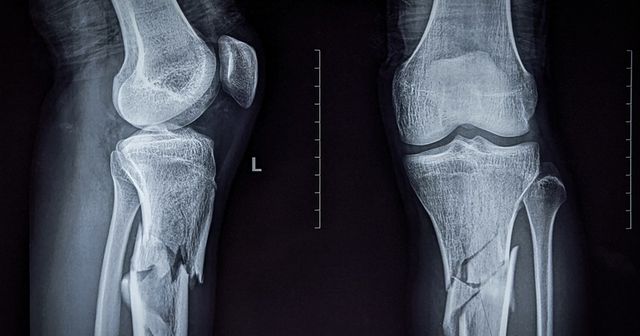

이영하는 2014년 뮤지컬 샤먼아이 리허설 도중 무대 장치 실수로 인해 고관절 골절 부상을 입었다. 당시 큰 충격을 받아 긴 치료 기간을 거쳤고, 이후 인공관절 수술까지 받으며 긴 회복 시간을 보냈다.

기사의 이해를 돕기 위한 사진 / Susmit Das-shutterstock.com

전문가들은 추락 사고로 인한 고관절 골절이 고령층에서 특히 위험할 수 있다고 경고한다. 고관절 골절은 심한 경우 거동이 어려워지고, 장기간의 침상 생활로 인해 근육 위축, 혈전증 등의 합병증 위험이 높아질 수 있다.

특히 회복 과정에서 재활 치료가 필수적이며, 인공관절 수술 후에는 지속적인 관리가 필요하다. 예방을 위해서는 미끄럼 방지 매트를 사용하는 등 생활 환경을 정비하고, 평소 근력 운동을 통해 근육을 강화하는 것이 중요하다.